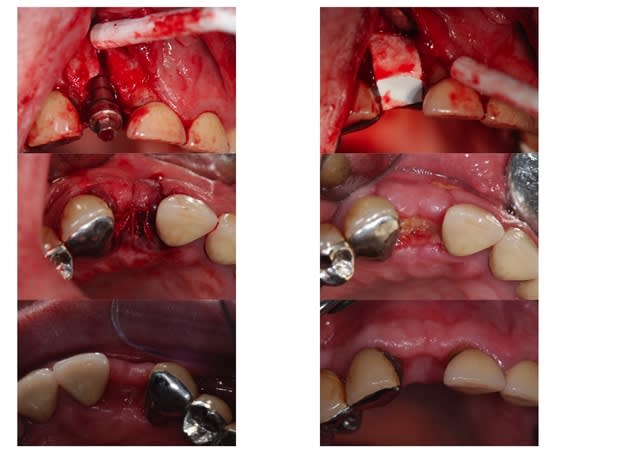

humator Ecrivait: > merci peach pour le diaporama. J'attend la > suite... >

la suite, la voici 5 mois + tard; la membrane de collagène a été exposée 10 jours + tard mais s'est finalement recouverte à 5 semaines post op bien que le ßTCP soit encore bien visible à la radio, j'ai accepté d'implanter à 5 mois sans plus attendre, pour satisfaire la demande du patient qui s'impatientait; évidemment, c'est discutable, mais dans la mesure où le TCP se résorbera un jour ou l'autre de toutes façons en laissant la place à del'os néo formé, j'ai accepté, en estimant que je ne devais normalement pas avoir de problème pour obtenir le fameux blocage primaire; effectivement, je l'ai eu à 40N/m, et avec une longueur de 13 mm, je suis serein; la paroi vestibulaire s'est bien reformée; le forage n'a pas été parfaitement centré, peut être parce que la dureté du site n'était pas uniforme, mais l'implant (ø 3,5mm) s'est recentré tranquillement au vissage (20 t/mn); tout est parfait à j+4; la suite suit... ! :-)